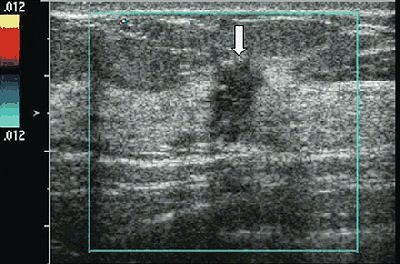

| US image and hemoglobin concentration maps of infiltrating lobular carcinoma (nuclear grade 2-3) located at 12 o'clock position in right breast of 37-year-old woman. Above, US image demonstrates lesion (arrow) measuring 1 cm in diameter. No blood vessels or blood flow were seen at color Doppler US. Below, total hemoglobin concentration map computed from absorption maps (not shown) obtained at 780 nm and 830 nm. Hemoglobin map reveals isolated high concentration mass in sections three (slice #3) and four (slice #4). Maximum hemoglobin concentration was 102.1 µmol/L, and average hemoglobin concentration was 68.7 µmol/L, as measured within FWHM region. Vertical scale presents total hemoglobin concentration in micromoles and ranges from 0 to 150 µmol/L. |